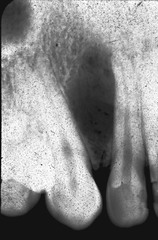

internal resorption

-round to ovoid radiolucency in the central part of the tooth -chronic inflammation -may see pinkish hue to crown if it is involved